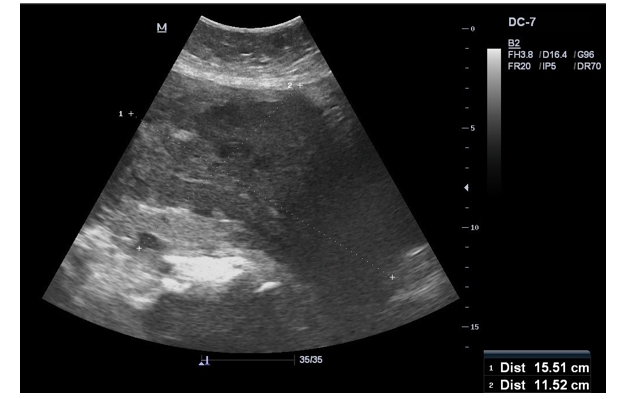

Ultrasound: Abdomen & Pelvis: Mottled heterogeneous appearing uterus, small myometrial lucent areas, with indistinct endometrial strip and pelvic intraperitoneal Fluid Figure 1. |

Adenomyosis is a benign gynaecological disease characterised by the presence of ectopic endometrium within the myometrium [8]. The diffuse nature of the disease, makes it very difficult to clinical¬ly diagnose patients with adenomyosis [17-19]. It typically affects multiparous women over 30 years of age and may cause dysmen¬orrhea, menorrhagia, and abnormal vaginal bleeding [17,18]. In our case series, patient B was multiparous 39-year-old female with similar clinical presentation. noted to have adenomyosis, on ultra¬sound image. (Figure 1) She underwent total abdominal hysterec-tomy with complete resolution of symptoms. Till date, hysterecto¬my remains the standard of care [8,17-29].

Figure 1: Adenomyosis